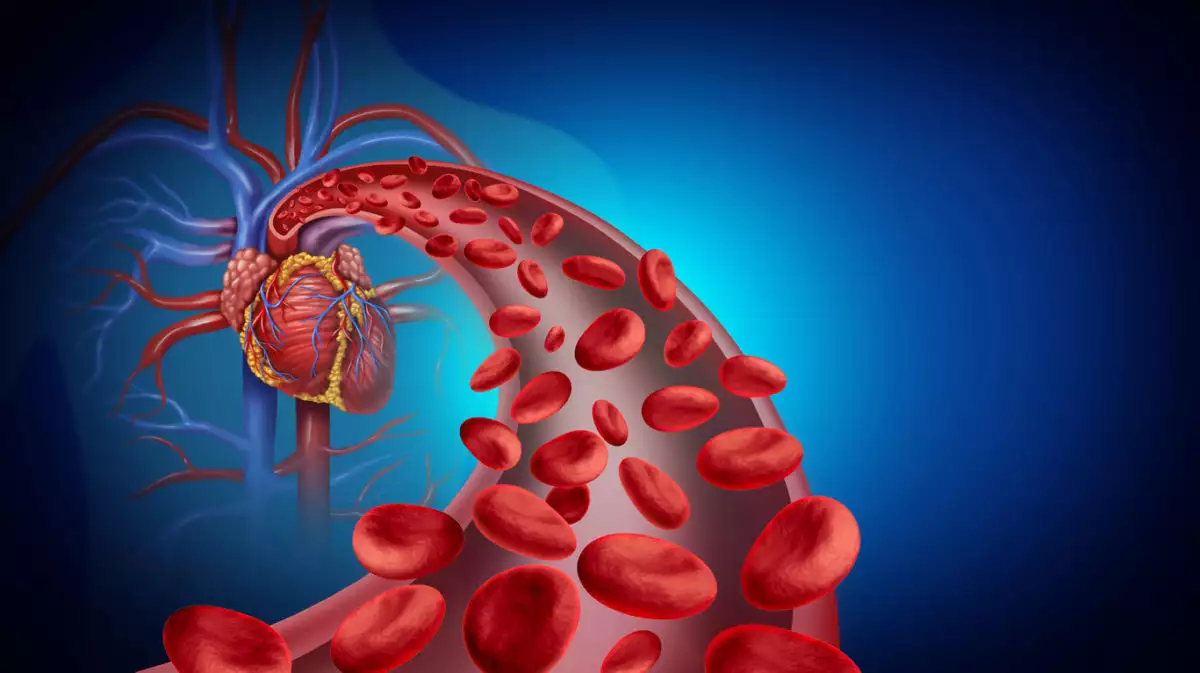

Η κακή κυκλοφορία του αίματος είναι μια κατάσταση που μπορεί να προκαλέσει διάφορα προβλήματα υγείας, μερικά από τα οποία μπορεί να είναι αρκετά σοβαρά.

Η σωστή ροή του αίματος εξασφαλίζει ότι το οξυγόνο και τα απαραίτητα θρεπτικά συστατικά μεταφέρονται σε όλο το σώμα, επιτρέποντας στα όργανα και τους ιστούς να λειτουργούν σωστά.

Όταν η κυκλοφορία παρεμποδίζεται, πολλές λειτουργίες του οργανισμού επηρεάζονται, προκαλώντας δυσφορία και μακροχρόνια προβλήματα υγείας.